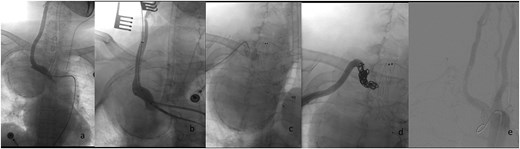

A 75-year-old female patient was admitted because of intermittent chest pain and dyspnea for 2 weeks. A thoracic aorta computed tomography angiography (CTA) demonstrated a large right proximal SAA with partial thrombosis, and the adjacent trachea, esophagus, and blood vessels were obviously compressed and displaced (Fig. 1). Physical examination revealed wheezing and phlegm sounds in the chest, and no obvious pulsatile mass was found in the right supraclavicular fossa.

Radiologic characteristics of the SAA. (a) Axial CTA demonstrates a bipartite aneurysm morphology with superior–inferior compartmentalization. The inferior spherical component measures 70.05 mm (long axis) × 69.73 mm (short axis), exhibiting regular contour and homogeneous attenuation. (b) The superior ellipsoid component displays dimensions of 51.81 mm (long axis) × 35.59 mm (short axis), with peripheral thrombus formation. (c) Coronal reformation reveals the characteristic gourd-shaped configuration and intraluminal thrombus burden. (d and e) Volume-rendered reconstructions delineate circumferential calcifications along the aneurysm wall, particularly prominent at the inflow/outflow transitional zone.